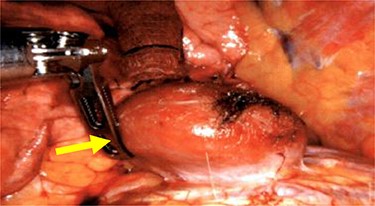

We performed a robotic thoracoscopy with plan for wedge resection and possible completion lobectomy. Gross inspection of the thoracic cavity revealed an abnormal mass on the dome of the diaphragm with the appearance similar to liver (Figs 5 and 6). The mass was noted to be positioned in the oblique fissure and correlated with the location of the larger nodule seen on CT scan. There was a second area of thinned-out diaphragm where a small nodule was noted to be protruding under the diaphragm. This second mass also had the appearance of liver and was consistent with location of smaller lesion on CT scan. A core needle biopsy was performed which was consistent with benign liver tissue. The decision was made not to proceed with any diaphragmatic repair or reinforcement with mesh. This was diagnosed as an asymptomatic herniation through the diaphragm, and the liver was fused to the diaphragm therefore preventing future intestinal herniation.

Liver herniation corresponding to the location of smaller lung nodule seen on CT scan.